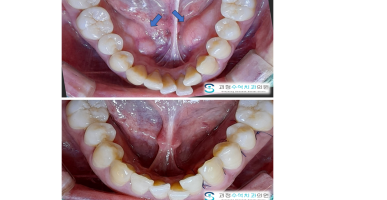

골융기제거술

혀아래쪽으로 울퉁불퉁한 잇몸뼈 골융기(토러스)를 제거한 사례입니다.